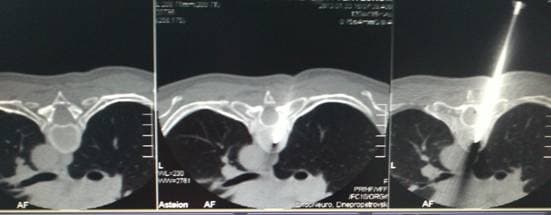

В нашем центре уже более 7 лет проводится пункционная вертебропластика с КТ с использованием компьютерного томографа или КТ – ассистенция, что позволяет нам выполнять вертебропластику у пациентов с переломами или гемангиомами тел позвонков верхнегрудного отдела позвоночника от Th1 до Th7 позвонков. Поскольку выполнить вертебропластику на этих уровнях под обычным рентгеновским контролем технически не представляется возможным из-за плохой визуализации позвонков на этих уровнях. Пункционная вертебропластика с КТ выполнения вертебропластики отличается только тем, что для интраоперационного контроля используется компьютерный томограф на котором установлена специальная программа позволяющая проводить такие манипуляции под чётким контролем. Внизу на фото представлены несколько клинических случаев.

Игла в теле позвонка

Позиционирование иглы в теле позвонка под контролем КТ